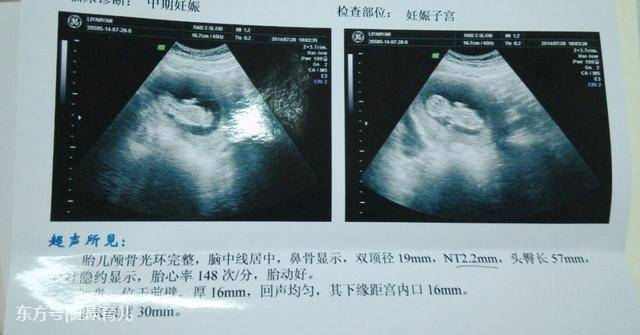

1、孕囊大小看胎儿性别

有传言说,如果孕囊大小的长和宽的相差在一倍以上,那么男宝宝可能性大。长和宽相等,或者相差不大的话,很可能是个女宝宝。有妈妈回顾起当年怀孕时的B超数据,来验证了一下,比如有位妈妈在怀孕8周时,孕囊大小是16mm×17mm,结果生下了一位小公主。

2、孕囊形状看胎儿性别

有人认为,孕囊形状可以看出胎儿是男是女。一般说来,如果孕囊的形状像茄子,或者是呈长条状的,则怀上男宝宝的可能性大;而如果孕囊是椭圆形或圆形的,那么很可能就是个女宝宝了。

3、胎心, 140以下男孩可能性大!150以上女孩可能性大!双顶径减股骨长,大于2.1是男孩,反之是女孩。